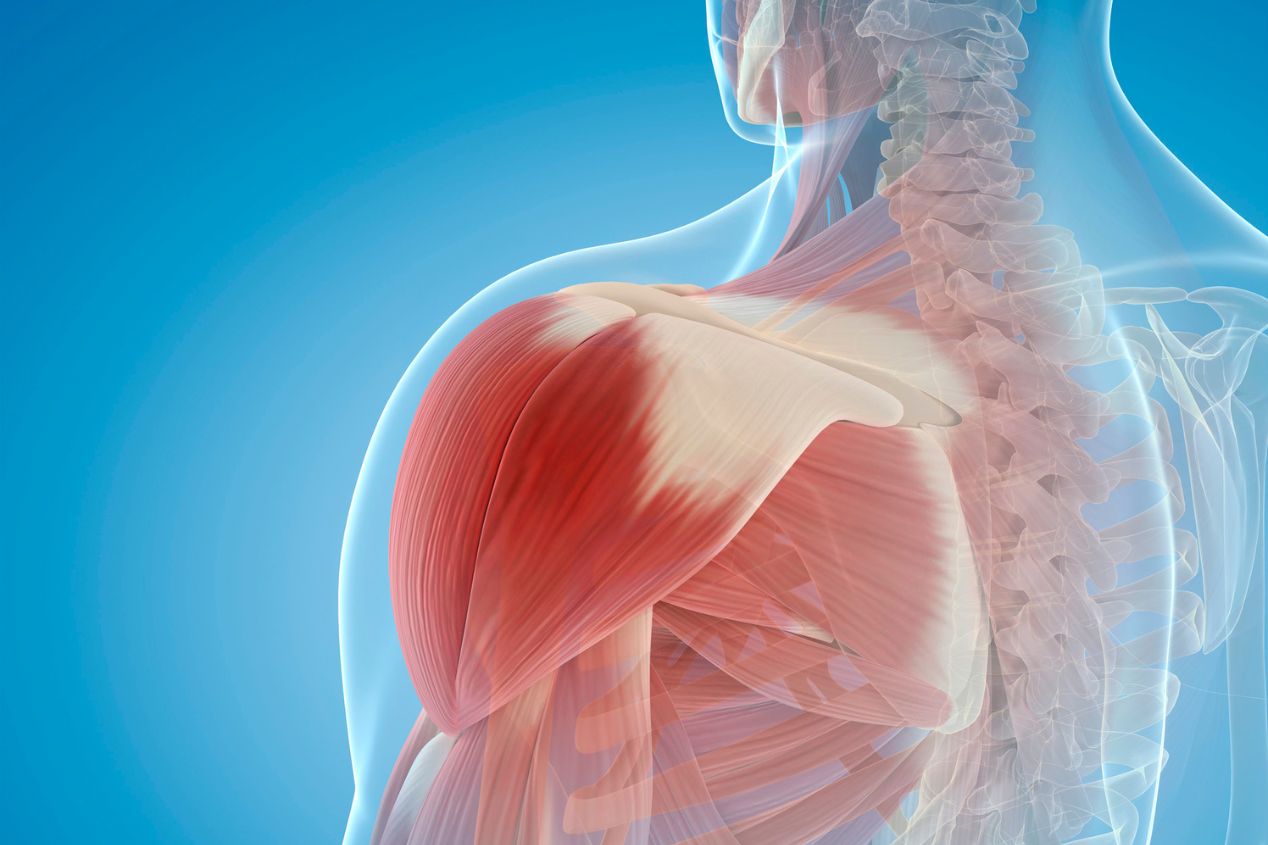

Σύνδρομο υπακρωμιακής προστριβής – Shoulder Impingement

Τι είναι το σύνδρομο υπακρωμιακής προστριβής ώμου; Το σύνδρομο  υπακρωμιακής προστριβής του ώμου είναι μια πολύ συχνή  παθολογία του  ώμου, που μπορεί να προκαλέσει πόνο, δυσκολία στην κίνηση και άλλα συμπτώματα που περιορίζουν την καθημερινή ζωή των ατόμων που την υφίστανται. Η υπακρωμιακή προστριβή συμβαίνει όταν ο υπακρωμιακός χώρος, που αποτελεί το διάστημα μεταξύ του ακρωμίου  οστού του ώμου  και του τένοντα του υπερακανθίου που βρίσκεται ακριβώς  στενεύει ή ερεθίζεται. Αυτό μπορεί να οδηγήσει σε φλεγμονή και πόνο.   Οι παράγοντες που μπορούν να συμβάλουν στην ανάπτυξη της συνδρομής υπακρωμιακής προστριβής περιλαμβάνουν υπερβολική χρήση του ώμου, τραυματισμούς ή  μη φυσιολογική ανάπτυξη ή διαμόρφωση του ακρωμίου και γενετικούς παράγοντες. Πώς γίνεται η διάγνωση υπακρωμιακής προστριβής; Η διάγνωση της υπακρωμιακής προστριβής γίνεται μέσω κλινικής εξέτασης, ακτινογραφιών και  μαγνητικής τομογραφίας. Η θεραπεία μπορεί να περιλαμβάνει αρχικά αντιφλεγμονώδη φάρμακα, φυσικοθεραπεία, αλλαγές στις καθημερινές συνήθειες για αποφυγή ερεθιστικών κινήσεων όπως μείωση της μεγάλης ανύψωσης του χεριού και σε ορισμένες περιπτώσεις που δεν βελτιώνονται τα συμπτώματα  αρθροσκοπική επέμβαση με κάμερα για διάνοιξη  του υπακρωμιακού χώρου. Το συνδρομο υπακρωμιακής προστριβής του ώμου είναι μια κατάσταση που μπορεί να προκαλέσει αναστάτωση στη ζωή ενός ατόμου λόγω του πόνου και των κινητικών δυσκολιών που προκαλούνται. Είναι πολύ σημαντικό να συζητήσετε με έναν εξειδικευμένο ιατρό ή  για την αξιολόγηση και τη θεραπεία της συνδρομής υπακρωμιακής προστριβής, προκειμένου να ανακτήσετε την κανονική κίνηση και την ποιότητα ζωής σας.